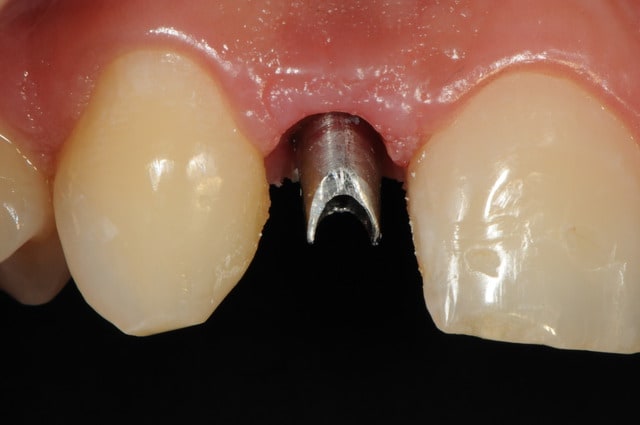

01/09/2010 à 16h54

-1 ou 2 mois plus tard ( je sais plus)

- empreinte avec transfert pop in

- pilier zircone esthétique Axiom

- prothèse et pilier

- pilier zircone en place

- couronne en place (petite compression gingivale)

fin du traitement